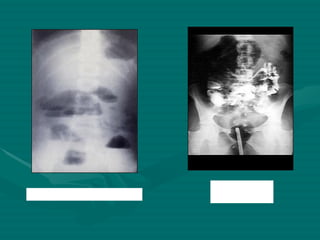

RADIOGRAFÍA SIMPLE DE ABDOMEN Hemos de evaluar la presencia de diversas anormalidades: Alteraciones del Patrón aéreo Aire  intraluminal Aire  extraluminal Íleo mecánico Íleo paralítico Abscesos Perforación libre Presencia de gas Masas  abdominales Calcificaciones

RADIOLOGIA Aunque no están estandarizadas, típicamente se realizan tres proyecciones abdominales:   *Decúbito supino.   *Bipedestación ( niveles hidroaéreos: Neumoperitoneo)  *Decúbitos laterales. Radiografía de abdomen simple de pie e xaminar rutinariamente:  Sombras de los Psoas.  Patrón aéreo intestinal.  Aire ectópico.  Líquido libre intraperitoneal. Abdomen Ag:  Util el uso de Contraste (sulfato de Bario) Contrastes hidrosolubles Yodado: Diferenciacion de Ileo mecanico con el Adinamico Enema Opaco de Colon:  Invaginacion Intestinal, Sospecha de Volvulo, Obstruccion intestinal.

RADIOGRAFÍA SIMPLE DEABDOMEN Hemos de evaluar la presencia de diversas anormalidades: Alteraciones del Patrón aéreo Aire intraluminal Aire extraluminal Íleo mecánico Íleo paralítico Abscesos Perforación libre Presencia de gas Masas abdominales Calcificaciones

RADIOLOGIA Aunque noestán estandarizadas, típicamente se realizan tres proyecciones abdominales: *Decúbito supino. *Bipedestación ( niveles hidroaéreos: Neumoperitoneo) *Decúbitos laterales. Radiografía de abdomen simple de pie e xaminar rutinariamente: Sombras de los Psoas. Patrón aéreo intestinal. Aire ectópico. Líquido libre intraperitoneal. Abdomen Ag: Util el uso de Contraste (sulfato de Bario) Contrastes hidrosolubles Yodado: Diferenciacion de Ileo mecanico con el Adinamico Enema Opaco de Colon: Invaginacion Intestinal, Sospecha de Volvulo, Obstruccion intestinal.